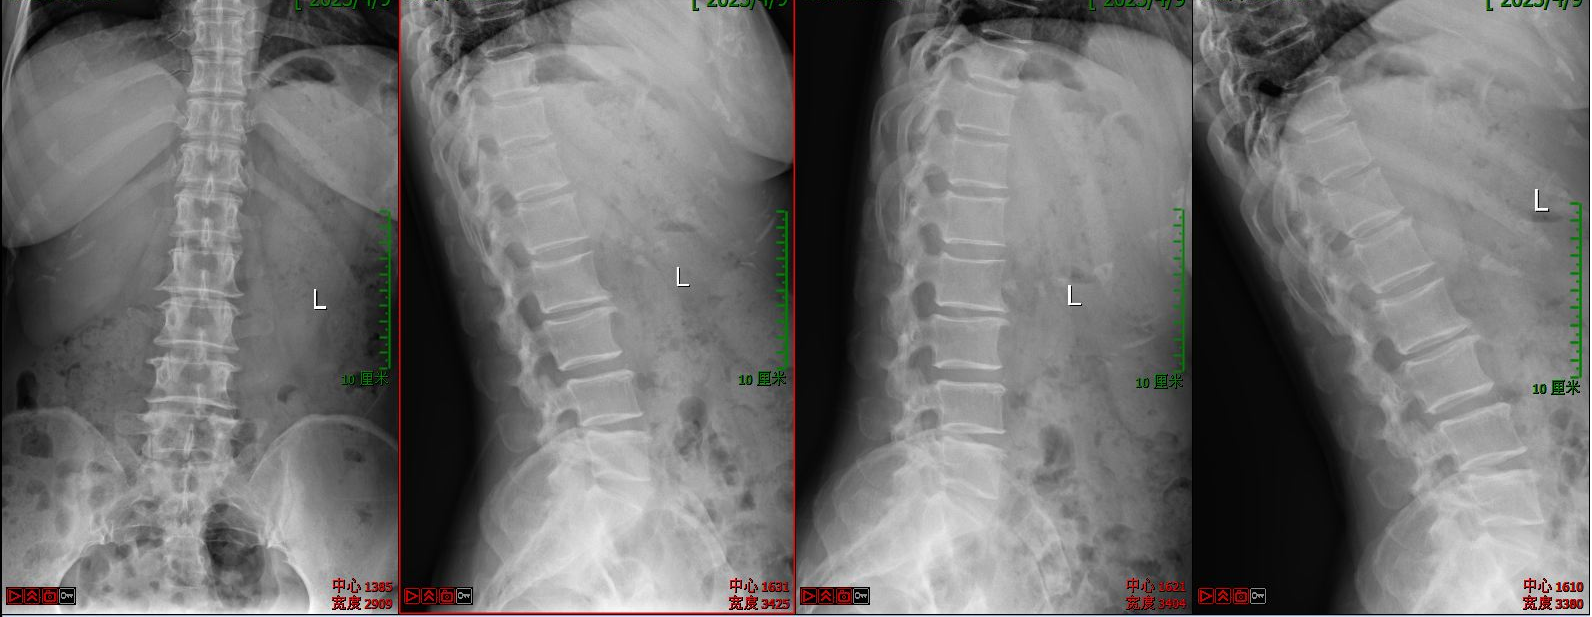

第一例病例为一名中年男性,腰4/5椎间盘突脱出并向下游离接近腰5/骶1椎间隙,为其实施VBE内镜下突出髓核单纯摘除术。患者术前腰痛伴右下肢疼痛麻木1个月余,右拇指背伸肌力明显下降。术后疼痛完全缓解,肌力较前部分恢复,有轻度麻木。

术前X线